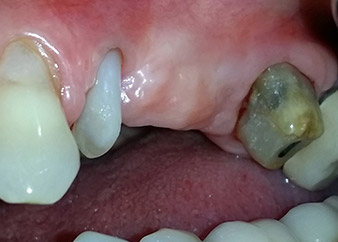

Mujer de 58 años de edad, que además es una apreciada colega y amiga, y se quejaba de dolor y de un aumento en la movilidad del pilar del puente de la pieza dental 24. También había inflamación periodontal, con bolsas de una profundidad de 7 mm en sentido mesiobucal y más de 12 mm en sentido distal, así como furcación de tercer grado. Asimismo, la radiografía reveló una lesión periodontal extensa alrededor de la región apical de la pieza dental 24 (figura 1) tratada previamente con endodoncia (alio loco).

Un mes después, en el día de la intervención, el dolor y la inflamación se habían reducido al mínimo en la pieza 24, pero seguía habiendo una movilidad de clase II de Miller. Después de la apertura de los colgajos y de la limpieza del tejido infectado periapical y perirradicular, la extensión del defecto óseo quedó evidente (figuras 2 y 3).

En la raíz bucal, faltaba todo el hueso vestibular y distal. Básicamente, la fijación se limitó a la raíz palatal, lo que corroboró el mal pronóstico preliminar. La pieza 27 también mostró una fijación horizontal reducida (figura 12) y una rarefacción apical mínima (figura 1), si bien sin síntomas clínicos.